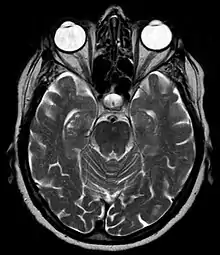

Hippocampal sulcus remnants seen on T2-weighted axial MRI image.

During human fetal development, the hippocampal sulcus first appears at approximately 10 weeks of gestational age. At this stage it exists as a broad shallow fissure along the surface of the dentate gyrus. Gradually, the fissure deepens and shifts toward the cornu ammonis. After about 18 weeks, the walls of the fissure fold into each other and begin to fuse. By 30 weeks, the hippocampal sulcus is normally obliterated except for its most medial part, leaving a shallow surface indentation.[1]